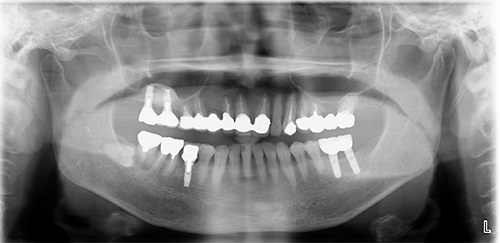

患者さんは他の医院で左下のインプラント治療をしましたが、上の奥歯は骨がないのでインプラント治療はできないとのことで紹介で来院しました。

赤い線が上顎洞です。骨造成(サイナスリフトが必要です。)